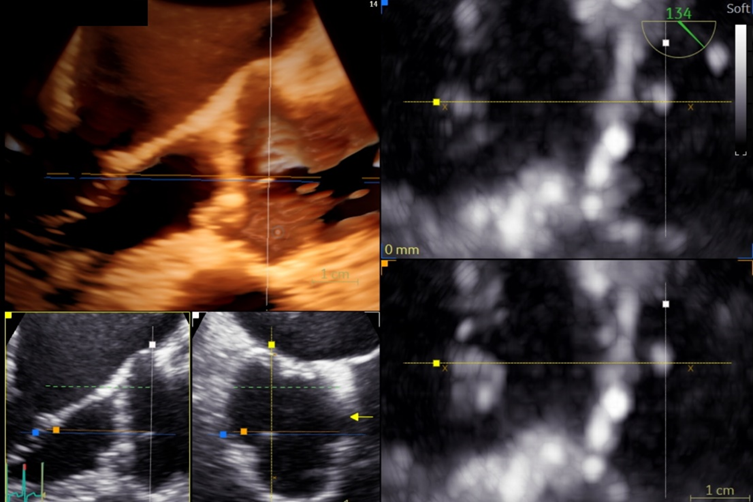

On the current presentation, the patient underwent repeat transthoracic echocardiography with bubble study and contrast-enhanced transthoracic echocardiography, neither of which demonstrated an intracardiac shunt or left ventricular thrombus. Electrocardiographically (ECG) synchronized cardiac computed tomography angiography (cCTA) was then performed as the final diagnostic test, supported by recent evidence demonstrating a higher diagnostic yield than echocardiography in the evaluation of acute stroke (Rinkel et al., 2022). cCTA revealed a 2-mm low-density tissue excrescence arising from the noncoronary cusp of the aortic valve (Figure 1) and simultaneously confirmed the absence of intracardiac thrombus or patent foramen ovale. Guided by cCTA localization, a repeat TEE with three-dimensional (3D) multiplanar reconstruction (Figure 2) successfully visualized the lesion. Intraoperative four-dimensional (4D) TEE with CT fusion—an innovative multimodality integration not previously described for this indication—was subsequently used for precise leaflet localization (Figures 3 and 4). Surgical pathology (Figure 5) demonstrated fibrocalcific degenerative changes of the noncoronary cusp and a small papillary fibroelastoma (PFE), which was deemed the most likely source of the patient’s recurrent cerebrovascular events.

Figure-2